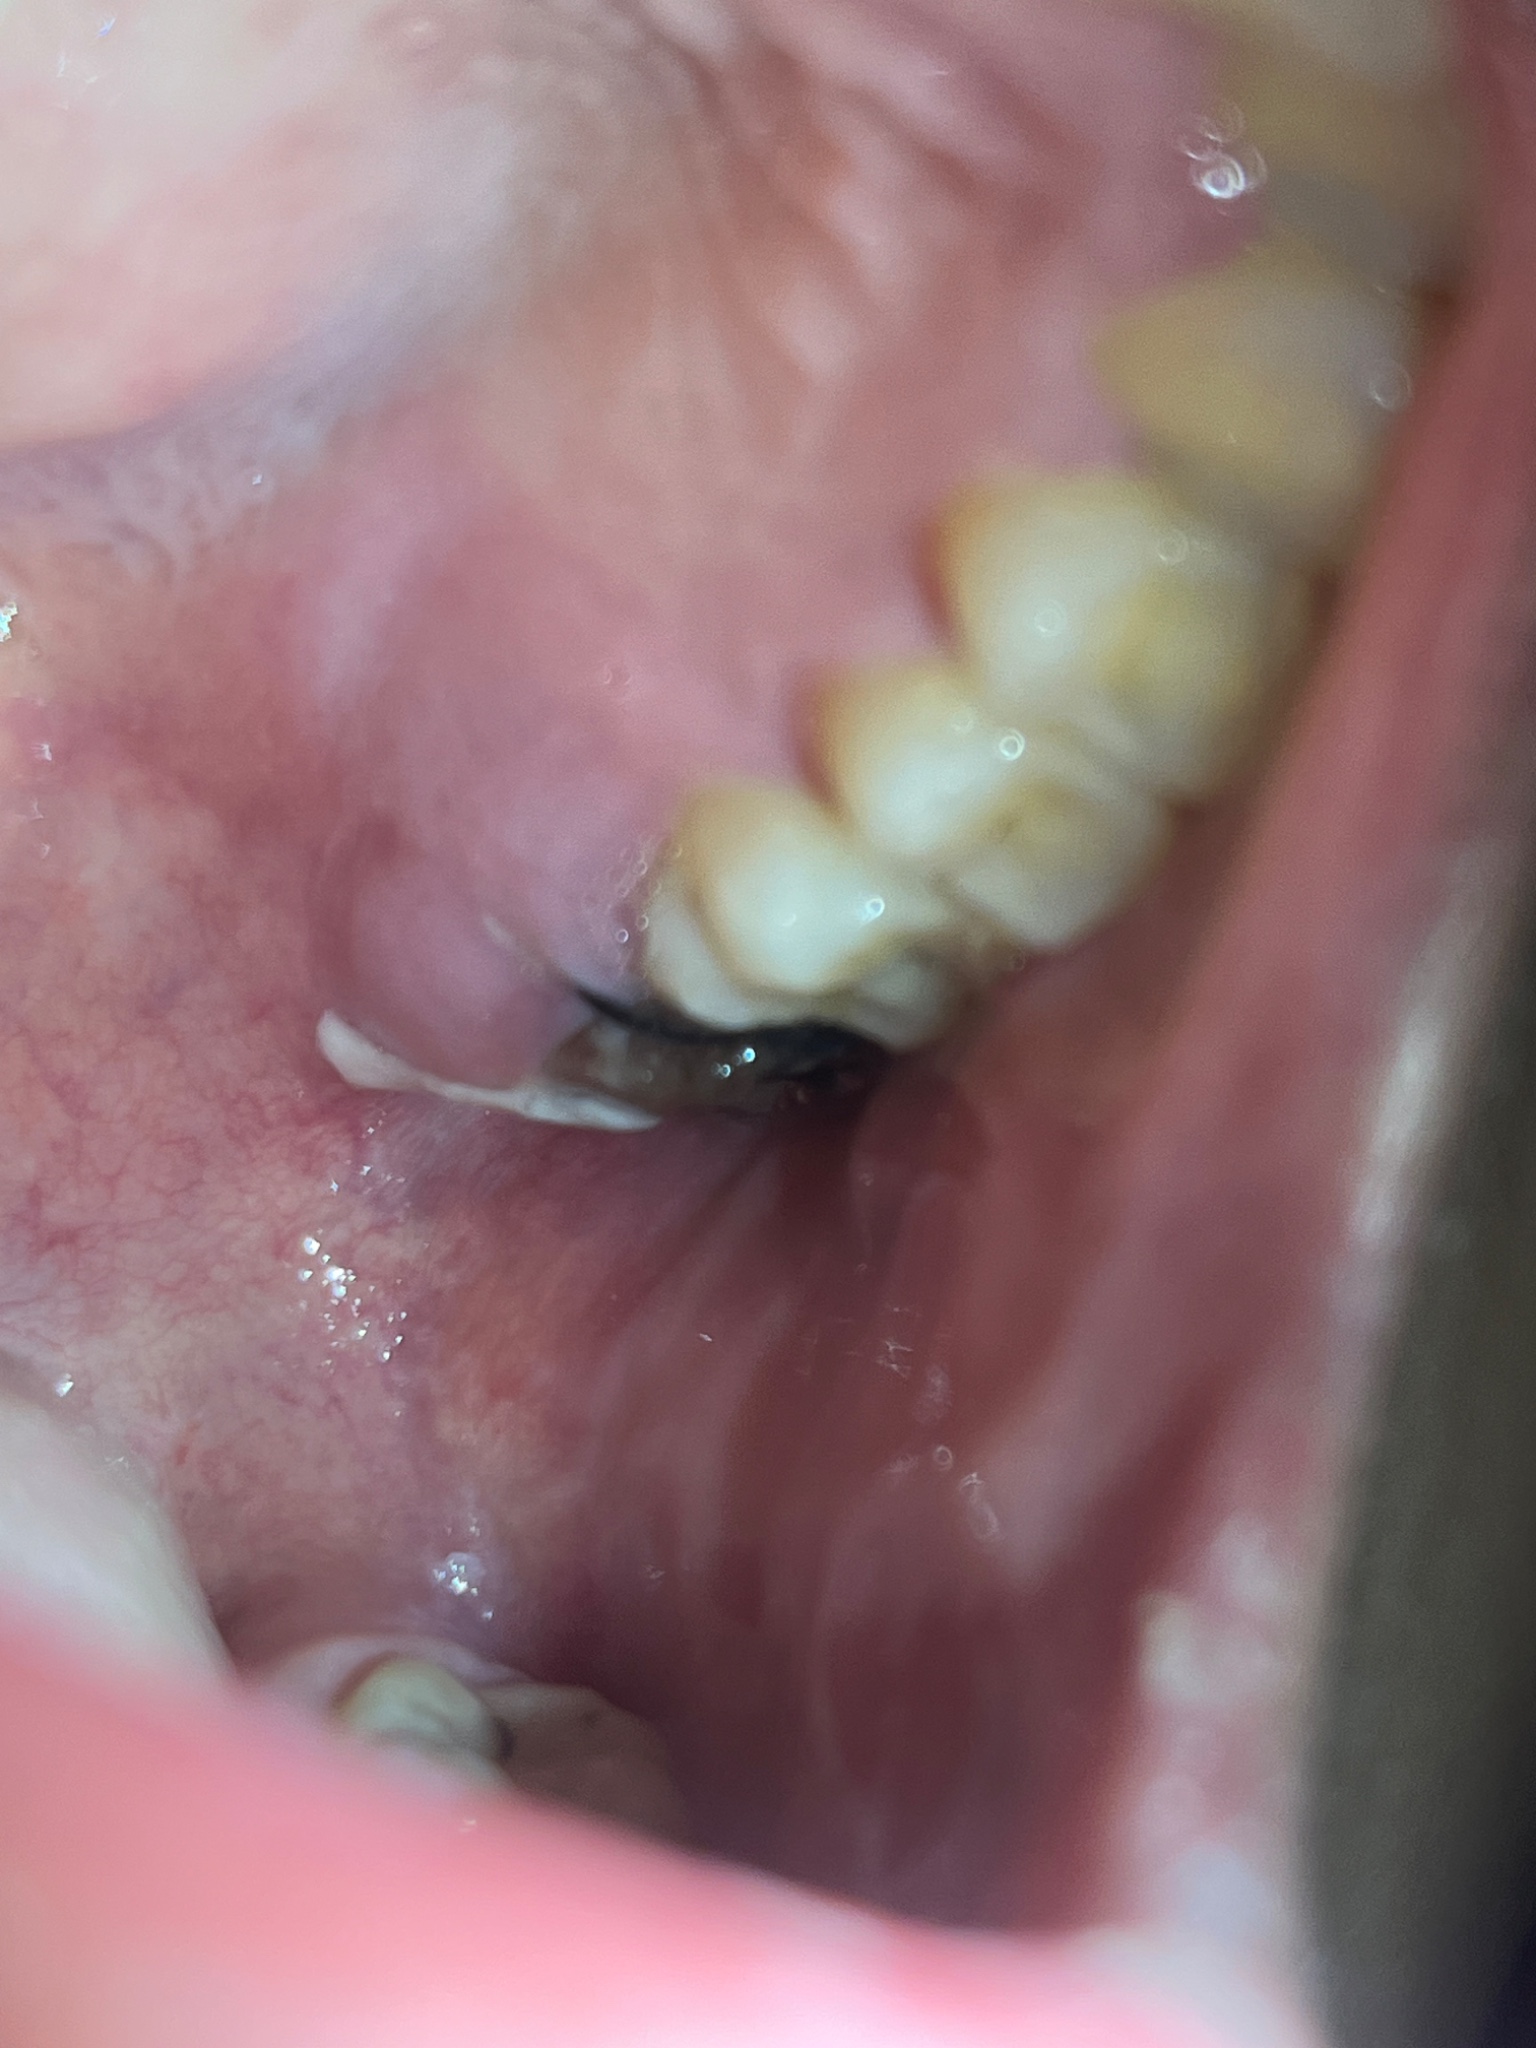

ตรงก้อนดำๆคืออะไรคะ แบบนี้ปกติดีมั้ย ไม่เคยถอนฟันแล้วต้องมาเย็บแผล ครั้งนี้ครั้งเเรกคะ เลยมีความกังวลกลัวจะเป็นหนอง แผลไม่ดี ตอนที่หมอจะเย็บคือกลัวมากเลยไม่ได้ฟังว่าเค้าทำอะไรบ้าง ใส่อะไรบ้างตอนเย็บ แล้วมันมีอะไรขาวๆอยู่ด้วย เวลาเอาลิ้นเขี่ยมันก็ขยับนะคะ แต่เวลาบ้วนปากก็ไม่ออกเลยคะ ใครมีความรู้หรือใครเคยผ่านจุดที่ถอนฟันแล้วต้องเย็บ ช่วยเเนะนำให้ความรู้ทีคะ คือตอนนี้กังวลมากเลย